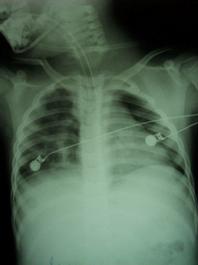

Pneumotorace sufocant bilateral Pneumotorace sufocant stang

Pneumotorace

sufocant stang Pneumotorace

sufocant drept Pneumotorace

sufocant drept